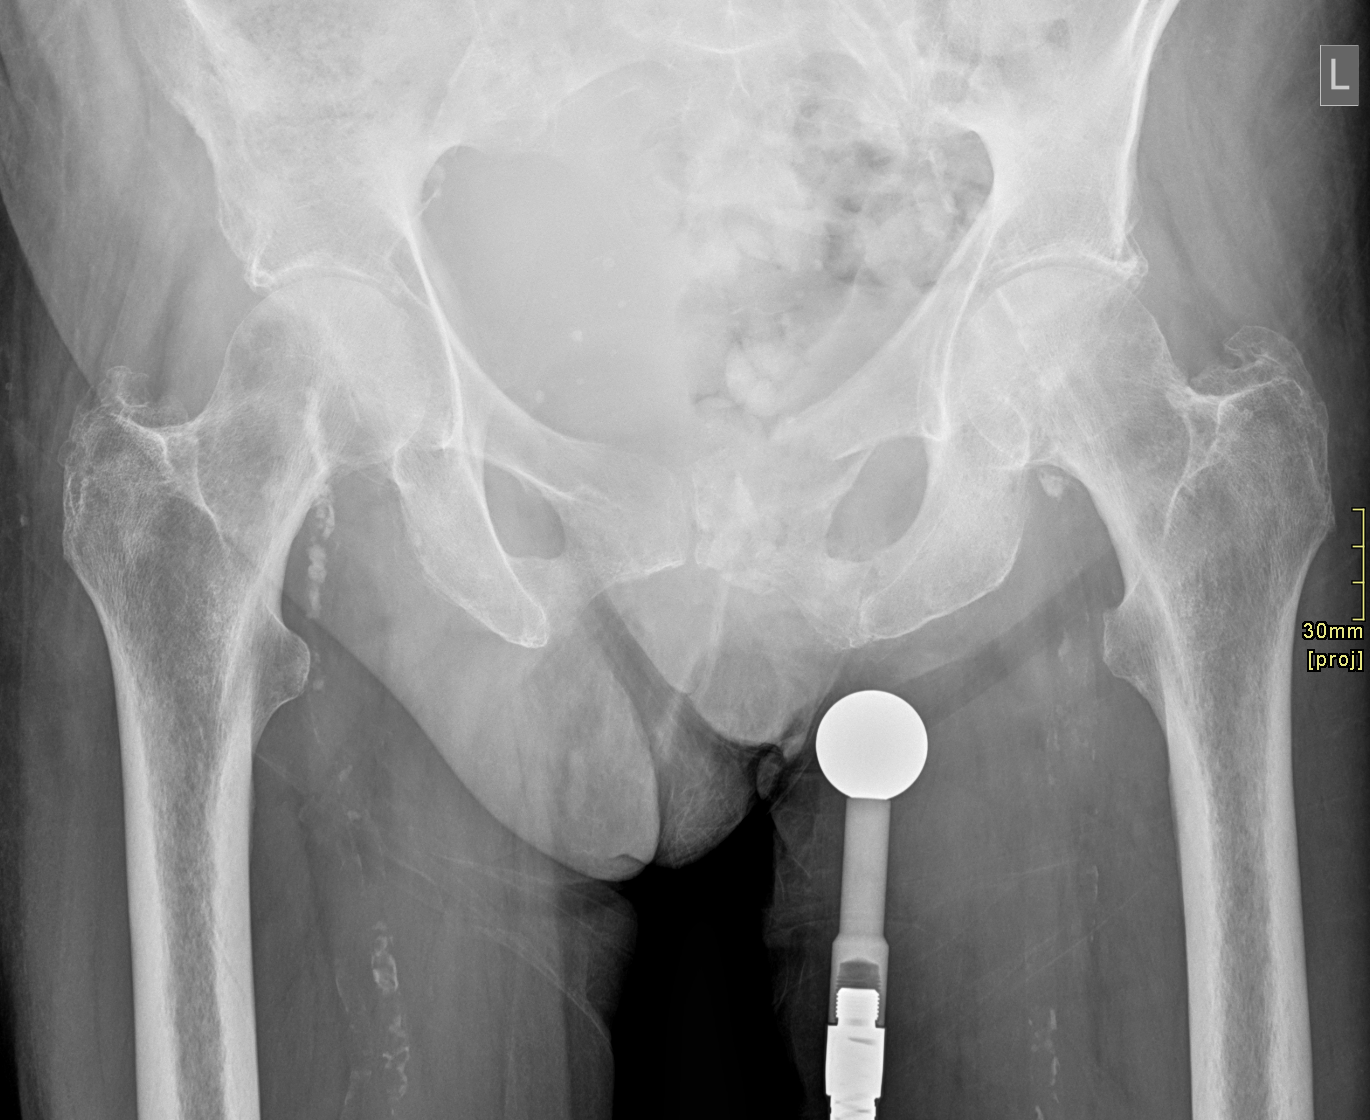

3. Left sided pubic ramal fractures